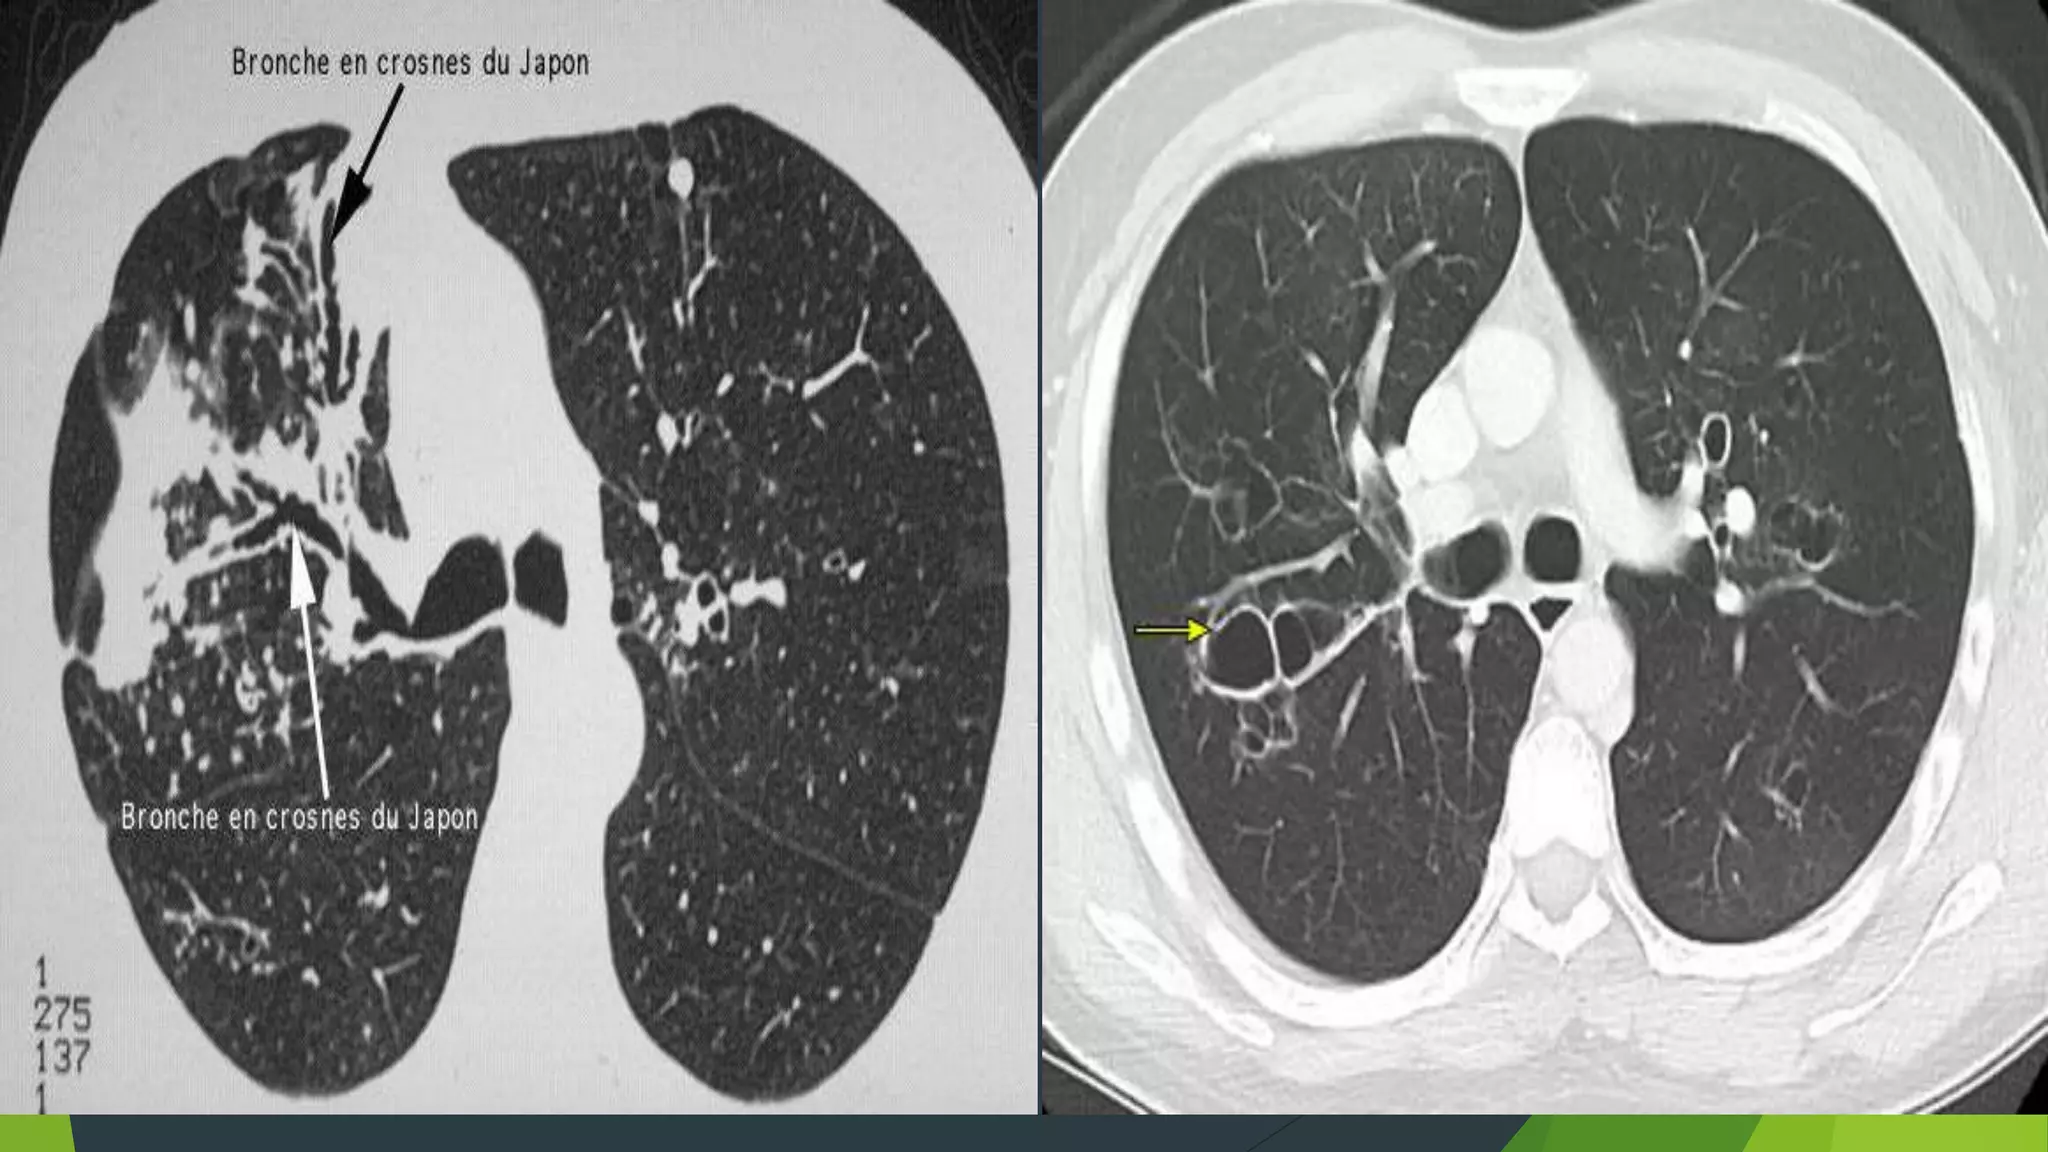

Hội chứng phế quản

 Dấu hiệu trực tiếp

- Dày thành phế quản (đường ray xe lửa, súng 2 nòng, phổi bẩn)

- Giãn phế quản (đường ray xe lửa, súng 2 nòng, giả tổ ong,...)

- Ứ đọng phế quản (dài mờ hình chữ V, Y, ngón tay đeo găng,...)

Dấu hiệu trực tiếp: Dày thành phế quản

 Bình thường các phế quản có

vách mỏng, không thấy trên X

quang qui ước, khẩu kính giảm

dần từ trung tâm ra ngoại vi.

 Khi phế quản bị dãn, vách dày

lên, trở nên song song với

nhau, cho ta hình ảnh đường

rầy xe lửa, hình ảnh này thấy

rõ hơn trên phim chụp cản

quang phế quản, hoặc phim CT

Dãn phế quản

 Dạng ống

 Dạng tràng

hạt

 Dạng kén

hoặc túi

X-Quang

-Biểu hiện các đám mờ hình ống do phế quản bị lấp đầy

chất nhầy

-Thành phế quản dày không đều , đường ray xe lửa, hình

súng hai nòng

- Có các ổ sáng nhỏ giống hình giả tổ ong, ổ sáng với

mức dịch

- 7- 30% giãn phế quản chụp phim phổi không thấy bất

thường

- CT là tiêu chuẩn vàng để chuẩn đoán giãn phế quản